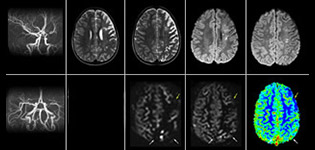

pCASL helps assess brain perfusion without contrast

Pseudo-continuous arterial spin labeling (pCASL) was developed for brain perfusion imaging without contrast agent. “This is very desirable in pediatric patients where the general trend is to limit the administration of contrast,” says Dr. Miller. Growing confidence in specific applications “We built up confidence in pCASL by comparing it to contrast-based perfusion imaging. Once we had confidence that it was representing what the contrast perfusions were representing, we increased our diagnostic confidence by serial imaging in either the acute stage or the long term stages in a number of patients with arterial abnormalities.

Dr. Miller uses pCASL for all patients who present with chronic and acute cerebrovascular abnormalities such as acute stroke, as well as patients who present with signs of acute inflammation in the brain, and occasionally in patients with tumors, to assess the perfusion status of their tumor.

“In combination with diffusion weighted imaging, it can help give a more extended assessment of the degree of perfusion abnormality in a patient who is suffering acute ischemia. We have a number of patients who have chronic arterial insufficiency due to prior arterial abnormalities or acquired arterial abnormalities such as sickle cell disease or neurofibromatosis. Sometimes the child’s first manifestation of disease progression is a reduction in brain perfusion before stroke symptoms manifest clinically or in diffusion weighted imaging. We use pCASL to help delineate the perfusion abnormality.”

To other new users I would recommend to also start to interpret the pCASL images in comparison with other standard imaging – T2 and FLAIR and DWI – until the user gains confidence in interpreting these images by themselves.” “A powerful use of pCASL is in patients with chronic cerebrovascular stenosis, where clinicians desire information on how compensatory mechanisms of the brain are performing to enable perfusion to the brain. Often clinicians take into account how the compensatory mechanisms appear to help to provide adequate perfusion to the patient’s brain, and they may intervene surgically or make some other management decision.” “Another special application is the assessment of cerebrovascular reactivity with a Diamox perfusion exam, where we subtract two sets of pCASL images.”

Efficiencies gained with pCASL

“pCASL has now become more of a first-line scan for assessing perfusion for us, as opposed to DSC-based perfusion imaging with contrast agent. And in patients who were not planned to have contrast, we can perform pCASL for perfusion imaging without need to stop the exam, pull the patient out, and put in an IV. It also negates the postprocessing that’s necessary for dynamic susceptibility contrasts. And it allows us to repeat perfusion imaging in the same patient at the same imaging time, which is helpful in terms of patient motion, or in a situation where a scan needs to be done before pharmacological perfusion imaging.”